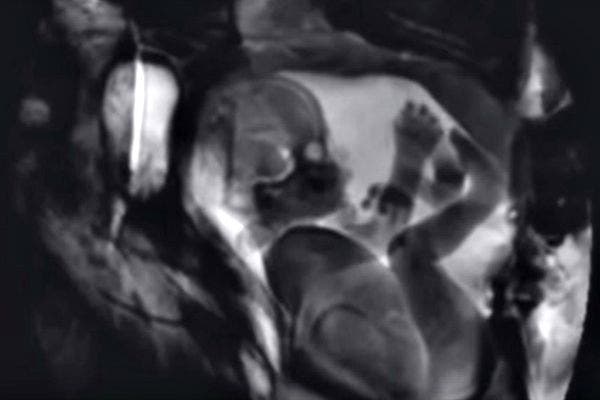

4. When a man and a woman love each other, they sometimes make a baby.

The MRI machine also captured a baby in utero. It's pretty amazing how much detail you can see on the baby — fingers, toes, eyes, and brain.

5. And sometimes, they're extra lucky and make two babies at once.

What's better than one baby? Two, of course! And you can already see who the bossy twin will be.